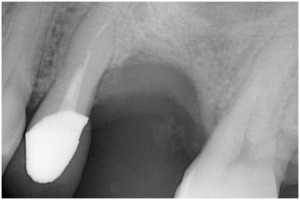

術前

同拡大

抜歯後

抜歯後GBR

GBR後

同拡大像